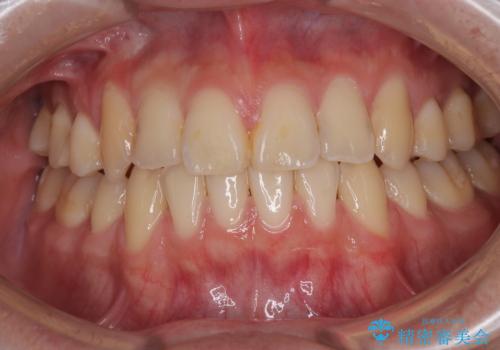

- 高校生の時に行った抜歯矯正の後戻りを気にして来院された患者様です。

インビザラインでの治療を希望されていて、デコボコの程度が中等度であり、安価なパッケージにて対応可能と判断されたため、インビザライン・モデレートを用いて矯正治療を行うこととしました。

インビザライン・モデレートは、製作できるアライナーの枚数に制限があるため、移動可能な量に限りがあるものの、インビザライン・ライトよりも枚数が多いため、幅広い症例に対応可能です。